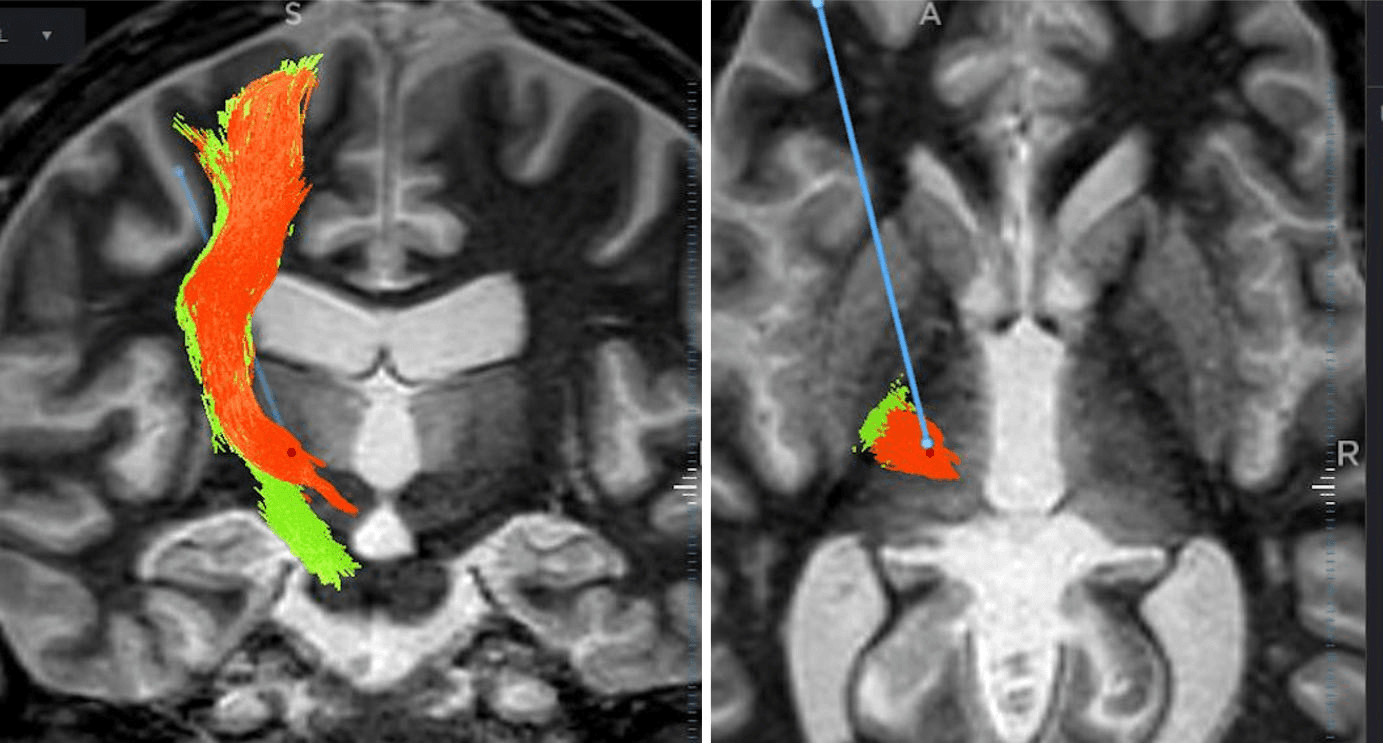

Enhanced visibility of relevant anatomy augments essential accuracy for treating functional indications